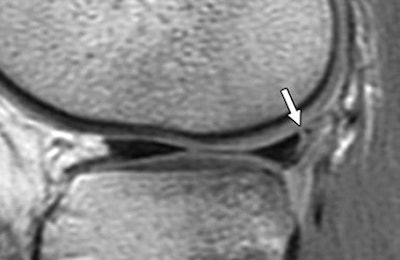

| A 15-year-old girl with originally missed longitudinal peripheral tear of posterior horn of lateral meniscus seen on retrospective review. Tear was repaired with sutures. Sagittal fast spin-echo proton density-weighted image shows peripheral longitudinal tear with vertical orientation (arrow). De Smet AA, Mukherjee R, "Clinical, MRI, and Arthroscopic Findings Associated With Failure to Diagnose a Lateral Meniscal Tear on Knee MRI" (AJR 2007; 190:22-26). |

While the authors could not come to any specific conclusions about why tears were missed, they cautioned that many had a longitudinal peripheral pattern with a vertical tear orientation. These tears are particularly unstable and can progress to bucket handle detachment, they cautioned.